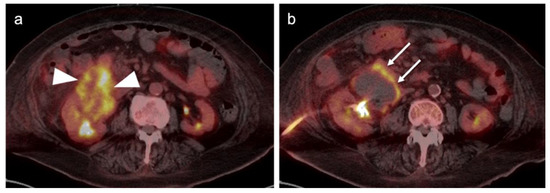

2.4. Cervical Cancer